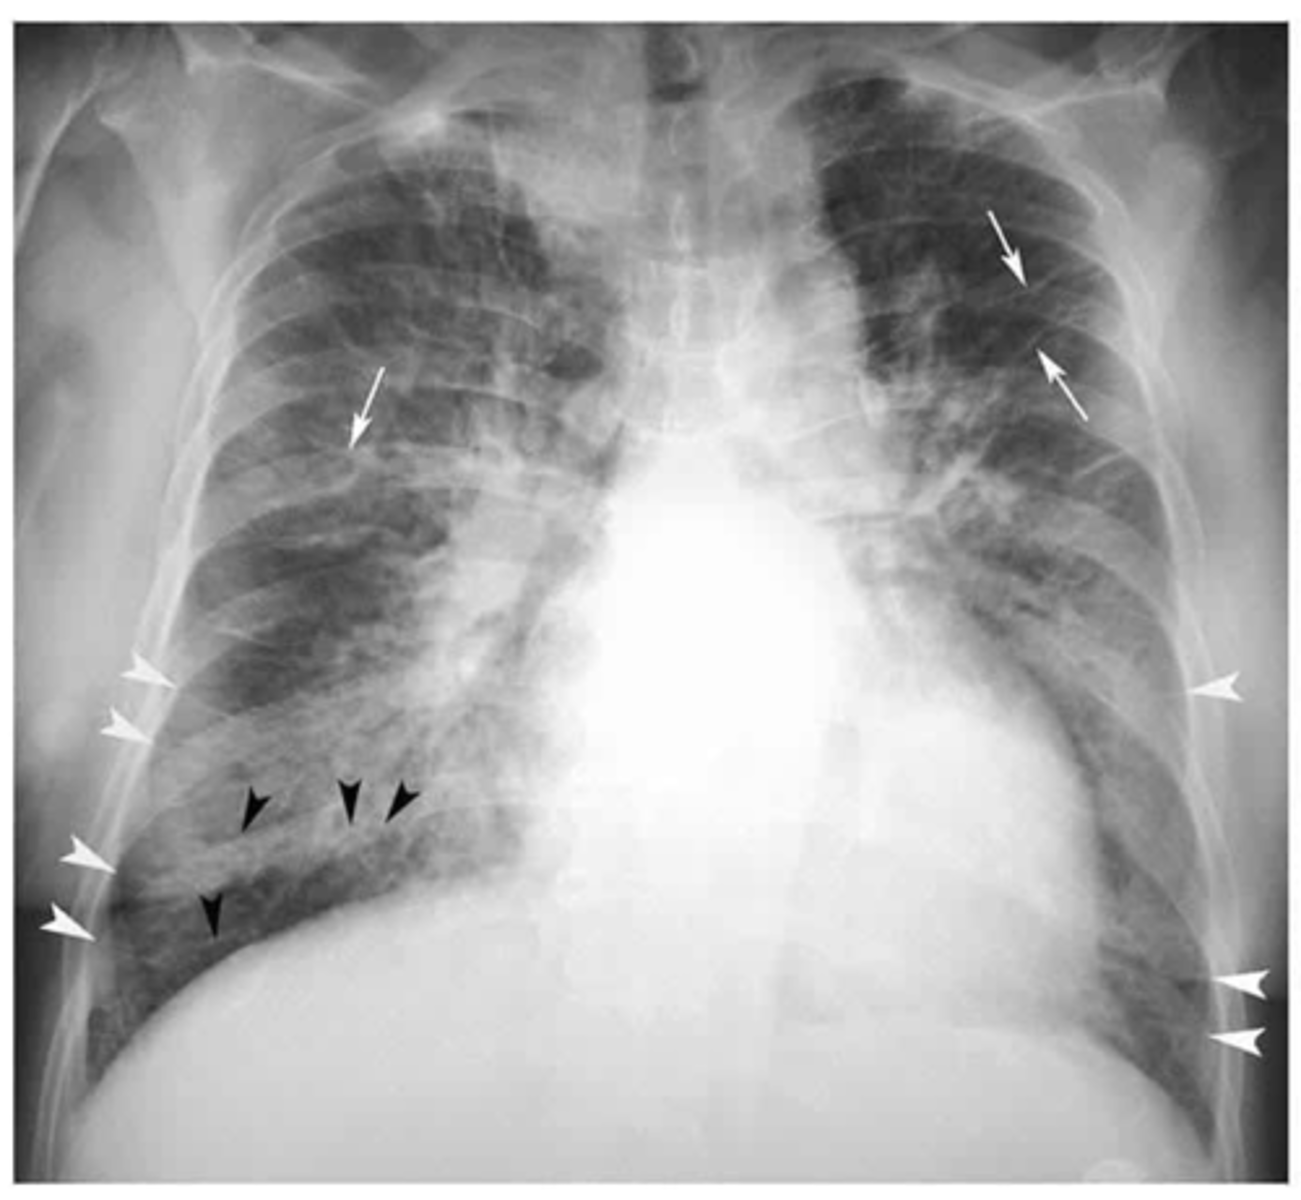

Black arrows: subcutaneous emphysema. White arrows: pneumomediastinum

ID black and white arrows

<p>ID black and white arrows</p>